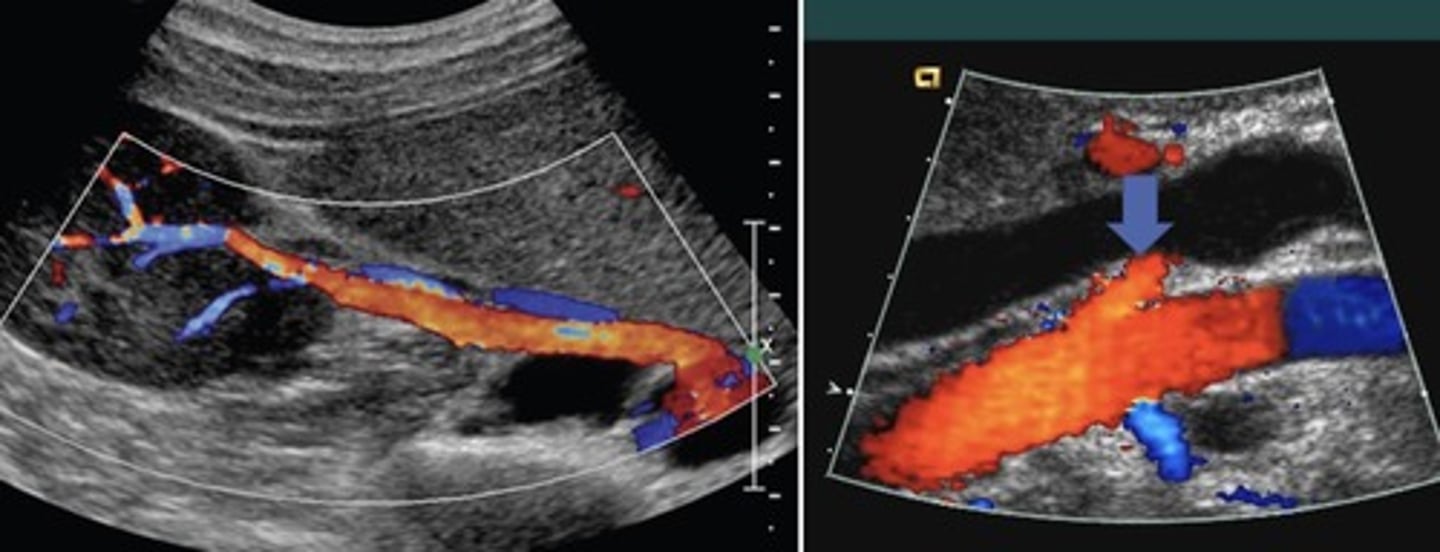

Coronary Vein Collateral

Can lead to esophageal varices

Recanalized Paraumbilical Vein

Ligamentum teres recanalizes

Courses from left portal vein to anterior abdominal wall

Hepatofugal flow

Splenorenal Shunt

Prominent veins at splenic hilum

Hepatofugal flow in splenic vein

Gastroesophageal Veins/Esophageal Varices

Originate from gastroesophageal junction posterior to left liver lobe

Due to hepatofugal flow in coronary vein shunt

High risk of rupture